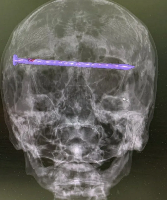

Изучение проблемы низкого качества рентгенограмм на Вашем оборудовании.

Любого доктора можно быстро подготовить как рентгенлаборанта и дать необходимые знания для оценки рентгенограмм.